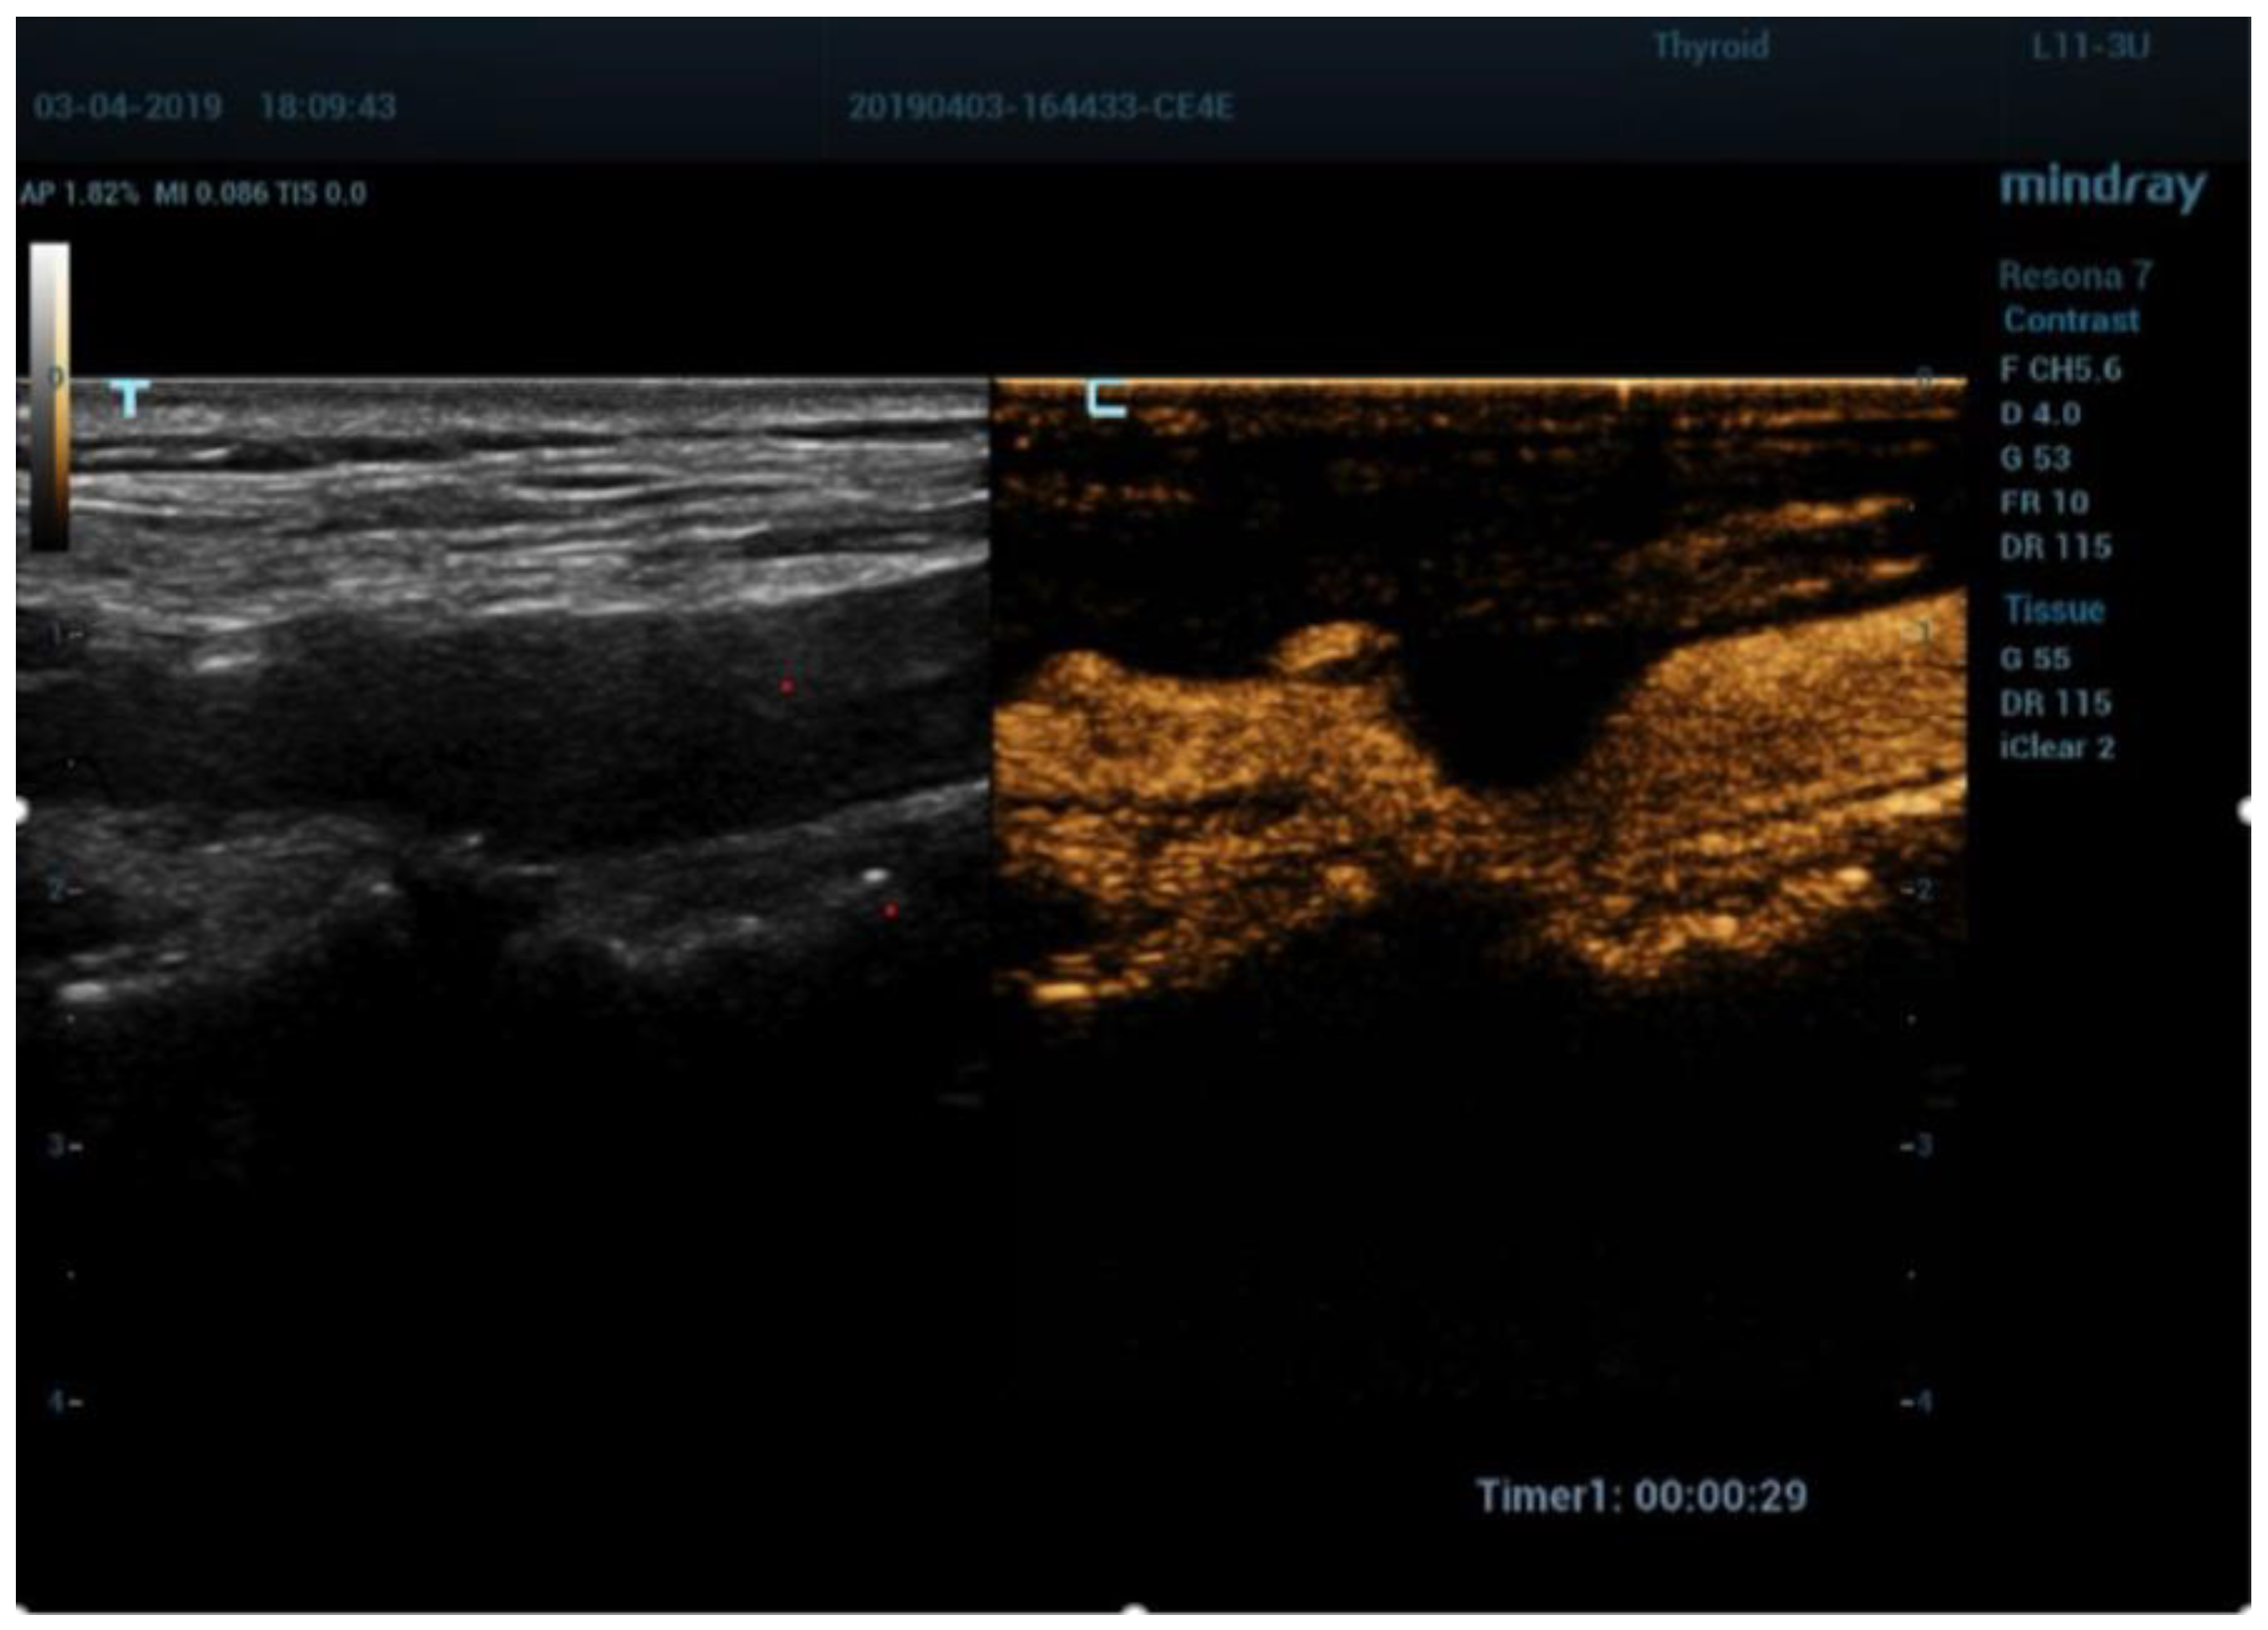

5. Contrast Enhanced Ultrasound (CEUS)